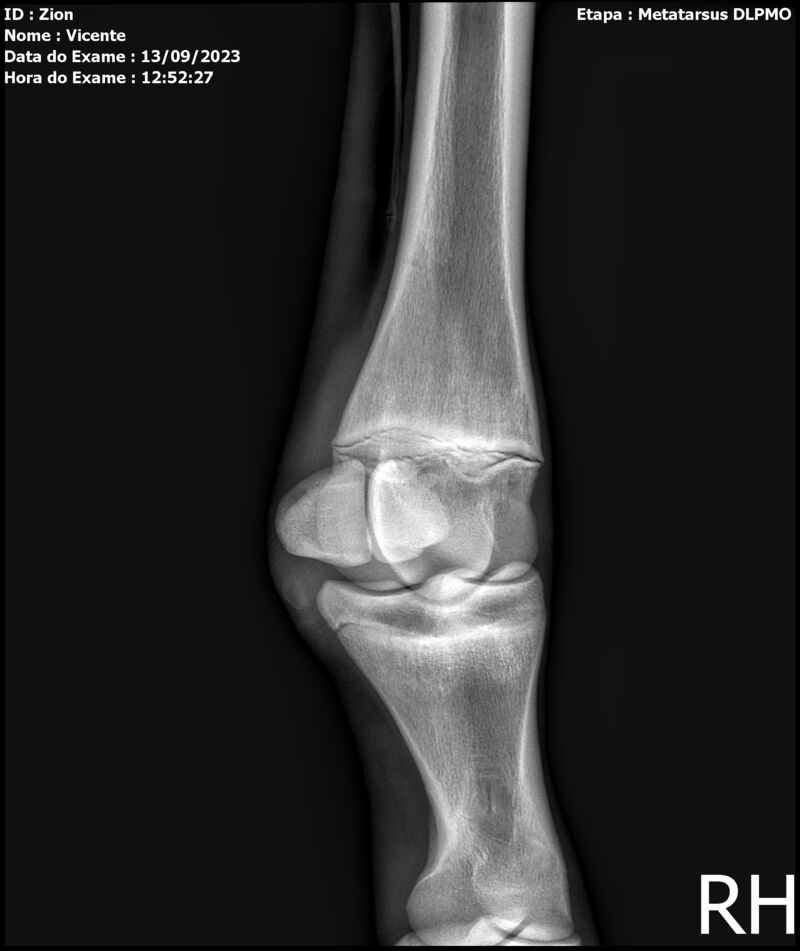

ZION ZC

Raça: BRASILEIRO DE HIPISMO

Sexo: MACHO - POTRO

Nascimento: 17/12/2022

Altura Aproximada: 1,51

Pel.: CASTANHO

Registro: EM AND

Vend.: VICENTE CONTE

Local : PORTO FELIZ/SP